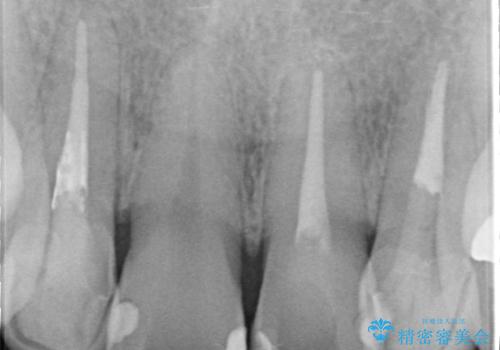

- 全体的なガタガタと前歯をきれいにしたいとのことで来院されました。

下の歯は重度のガタガタがあり、上の前歯は何本かが神経の治療がしてある状態でした。

インビザラインにて歯並びを整え、上顎の前歯にセラミックを装着する計画としました。